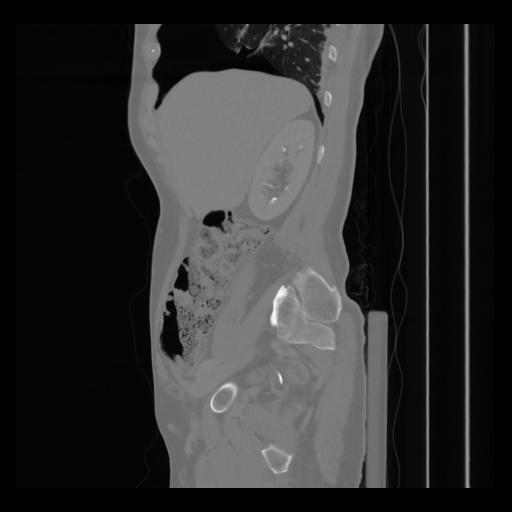

36 CUERPO,CE,Sagittal,3.000,CUERPO,Sagittal,